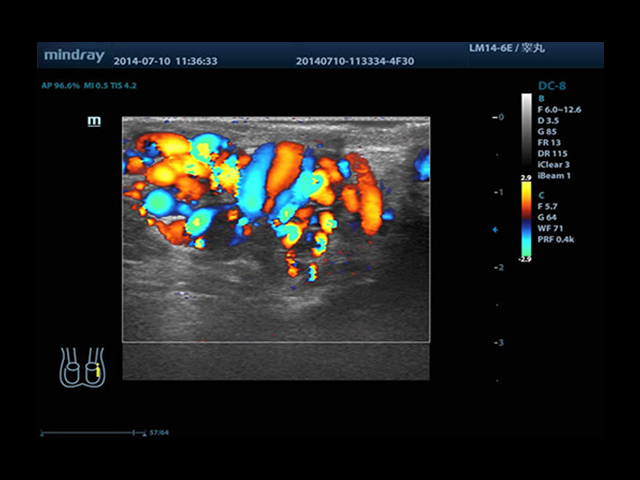

Mindray DC-8 Exp оснащен новым поколением датчиков с увеличенным количеством элементов и инновационной технологией "3T". Это позволяет достичь высокой детализации и качества изображения. Благодаря новейшей технологии iFlow, можно визуализировать даже самые мелкие сосуды и кровеносные пути.

Сверхширокополосная нелинейная обработка изображений снижает визуальные шумы на 30% по сравнению с другими системами. Технология iClear позволяет устранить зернистость изображения, а iBeam (технология пространственного компаундинга) обеспечивает высокое качество сканирования органов и тканей под различными углами.

• Natural Touch Elastography - опция оценки эластичности ткани (эластография), с программой анализа. Действует на линейных и внутриполостных датчиках. Компрессионный метод.

• Small parts package - предустановленные параметры, аннотации, маркеры, программы измерений для исследования малых (поверхностных) органов